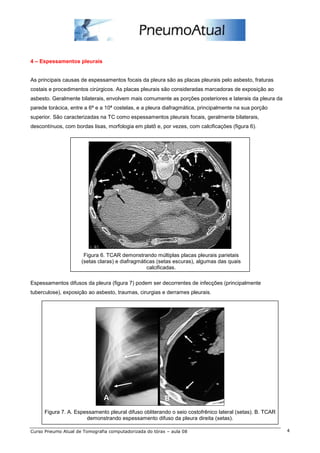

As principais causas de espessamentos focais da pleura são as placas pleurais pelo asbesto, fraturas

costais e procedimentos cirúrgicos. As placas pleurais são consideradas marcadoras de exposição ao

asbesto. Geralmente bilaterais, envolvem mais comumente as porções posteriores e laterais da pleura da

parede torácica, entre a 6ª e a 10ª costelas, e a pleura diafragmática, principalmente na sua porção

superior. São caracterizadas na TC como espessamentos pleurais focais, geralmente bilaterais,

descontínuos, com bordas lisas, morfologia em platô e, por vezes, com calcificações (figura 6).

Figura 6. TCAR demonstrando múltiplas placas pleurais parietais

(setas claras) e diafragmáticas (setas escuras), algumas das quais

calcificadas.

Espessamentos difusos da pleura (figura 7) podem ser decorrentes de infecções (principalmente

tuberculose), exposição ao asbesto, traumas, cirurgias e derrames pleurais.

Figura 7. A. Espessamento pleural difuso obliterando o seio costofrênico lateral (setas). B. TCAR

demonstrando espessamento difuso da pleura direita (setas).